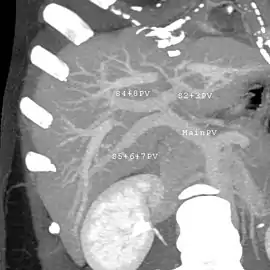

With the recent advances of noninvasive imaging, living liver donors usually have to undergo imaging examinations for liver anatomy to decide if the anatomy is feasible for donation. The evaluation is usually performed by multidetector row computed tomography (MDCT) and magnetic resonance imaging (MRI). MDCT is good in vascular anatomy and volumetry. MRI is used for biliary tree anatomy. Donors with very unusual vascular anatomy, which makes them unsuitable for donation, could be screened out to avoid unnecessary operations.